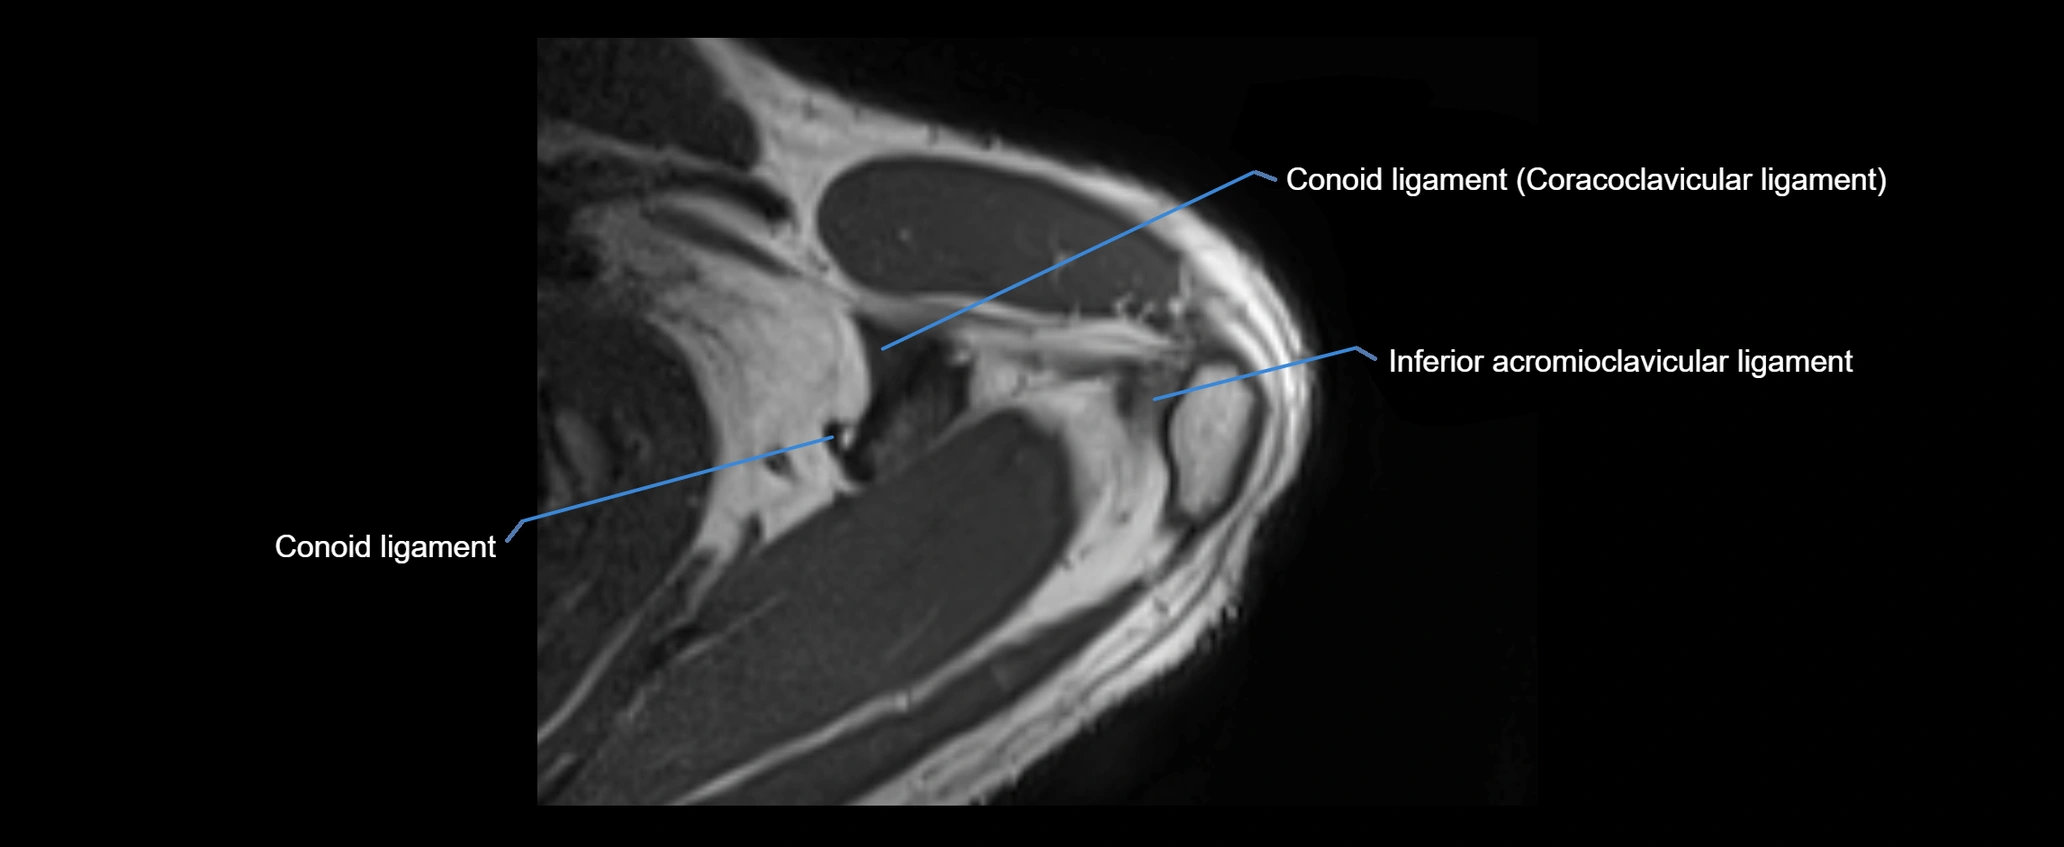

MRI images

image